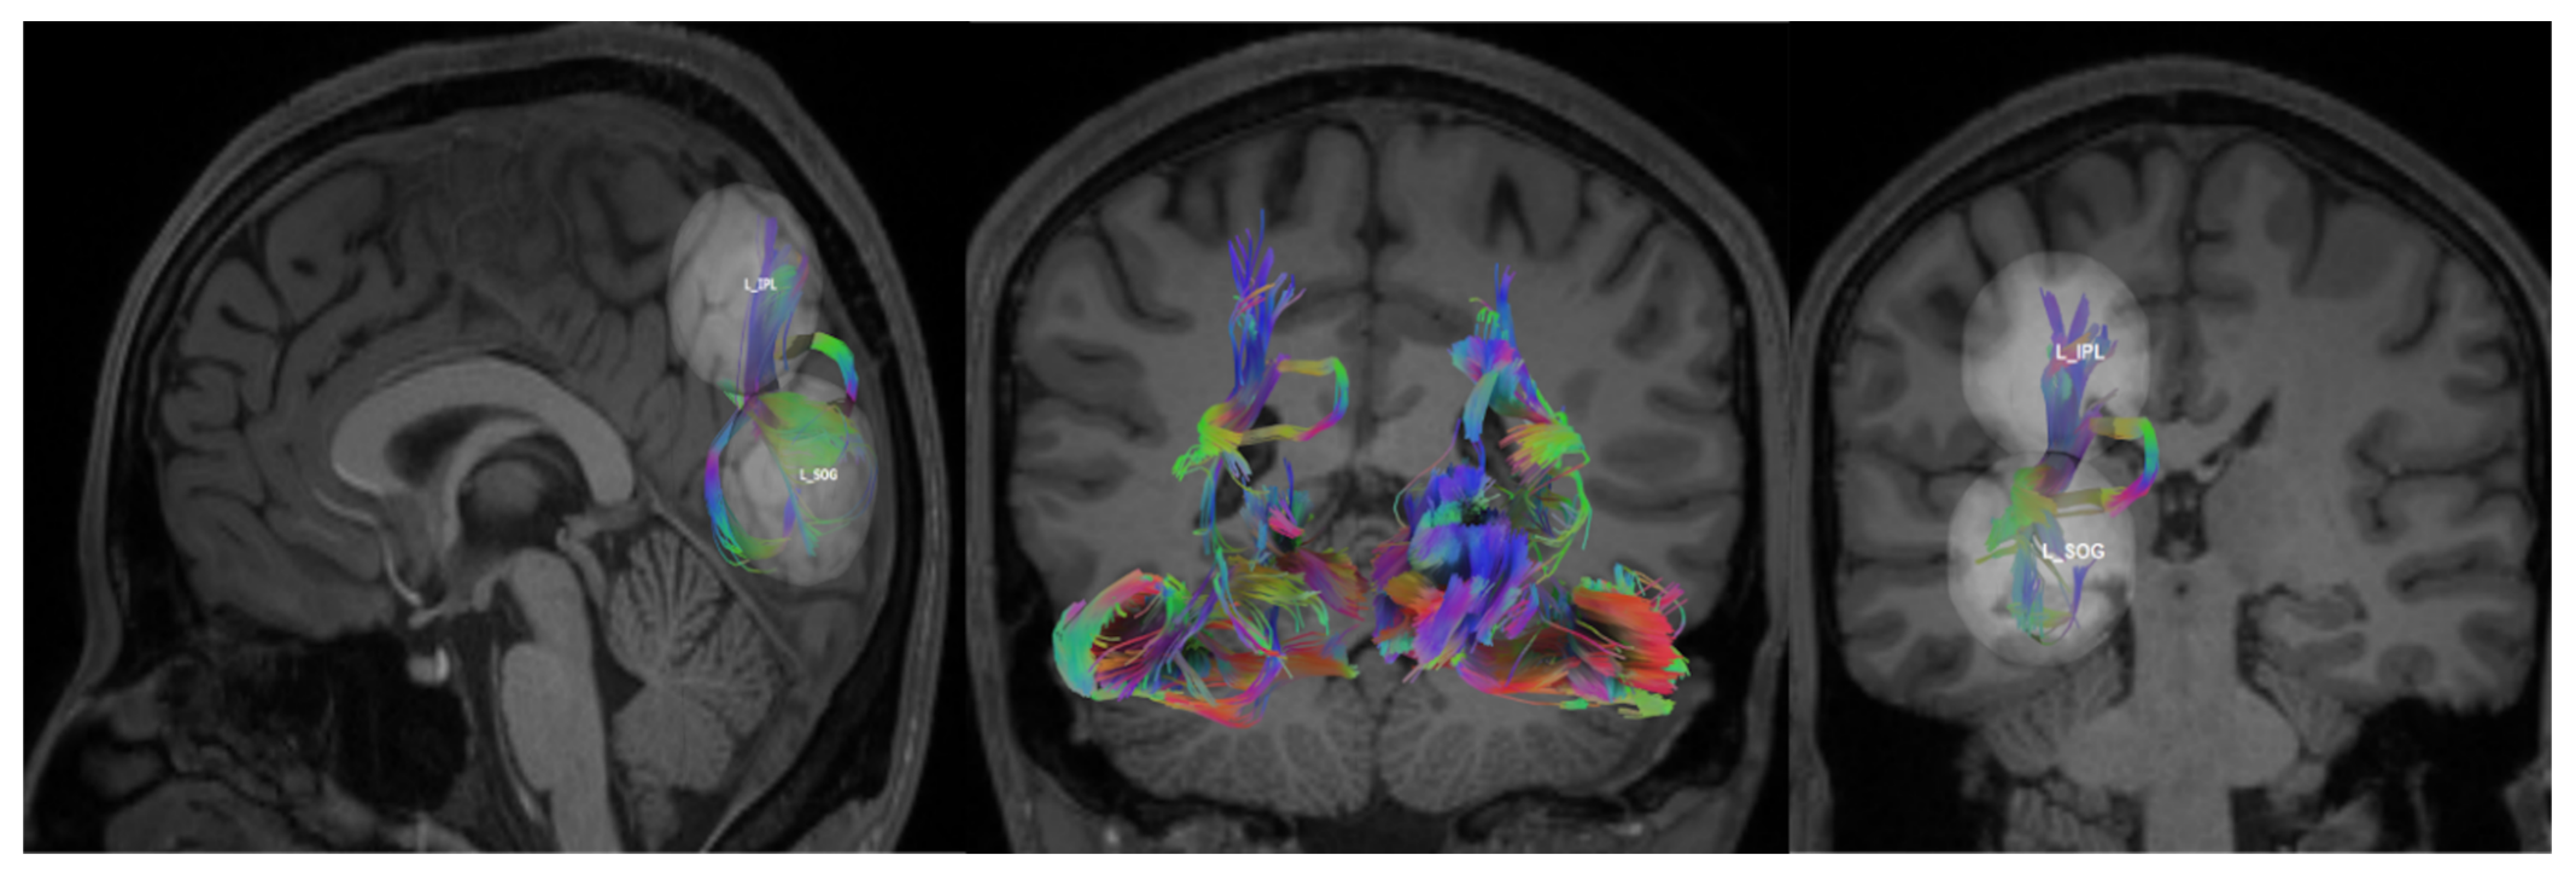

| DVS | L SOG L IPL | 10 | 100 | 60 |

| L SOG L SPL | 10 | 300 | 70 | |

| Left superior occipital gyrus (L SOG) | −26, −73, 23 | DVS, VS |

| Left inferior parietal lobule (L IPL) | −24, −52, 52 | DVS |